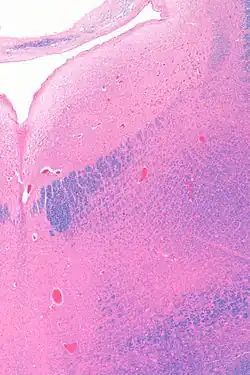

Micrograph showing the locus coeruleus. HE-LFB stain

The locus coeruleus (LC) is located in the posterior area of the rostral pons in the lateral floor of the fourth ventricle. It is composed of mostly medium-size neurons. Melanin granules inside the neurons contribute to its blue colour. Thus, it is also known as the blue nucleus, or the nucleus pigmentosus pontis (heavily pigmented pontine nucleus).[5] The neuromelanin is formed by the polymerization of norepinephrine and is analogous to the black dopamine-based neuromelanin in the substantia nigra.